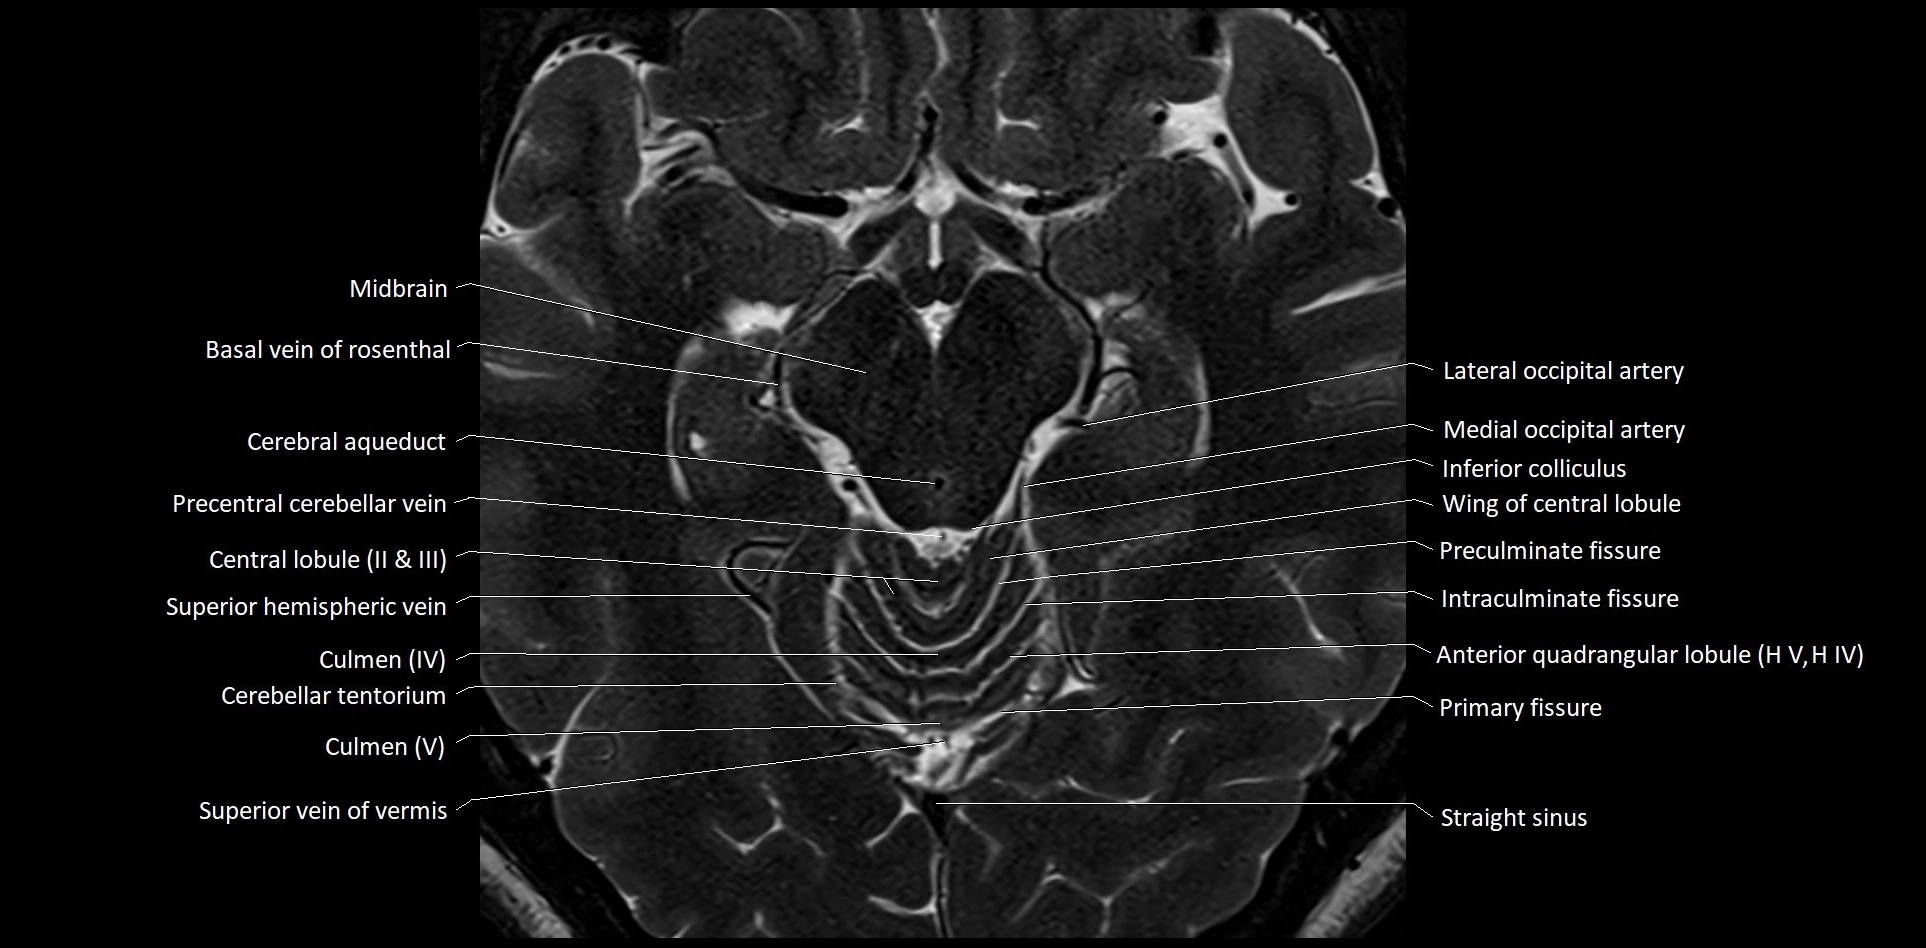

MRI images